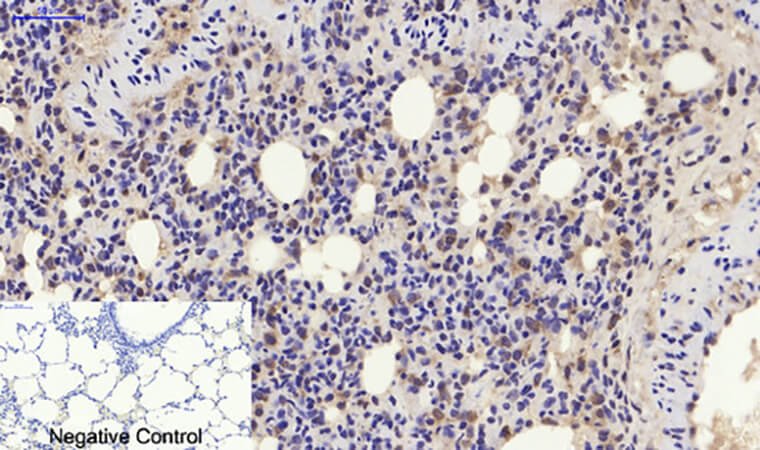

For Immunohistochemistry (IHC) on FFPE sections: Antigen retrieval is non-negotiable—use citrate buffer (pH 6.0, 20 min, 95°C) to unmask the N-terminal epitope. Dilute 1:500 (overnight at 4°C) and pair with a polymer detection kit (e.g., Abbkine’s KTD3010). In p21 IHC for prostate cancer, expect strong nuclear staining in high-grade tumors (Gleason score ≥8); counterstain with hematoxylin to highlight basal cell layers. Funny enough, a lab fixed “no signal” in mouse liver by realizing their sections were over-fixed (24 hrs in formalin vs. 12)—ABP0108 hates excessive crosslinking!